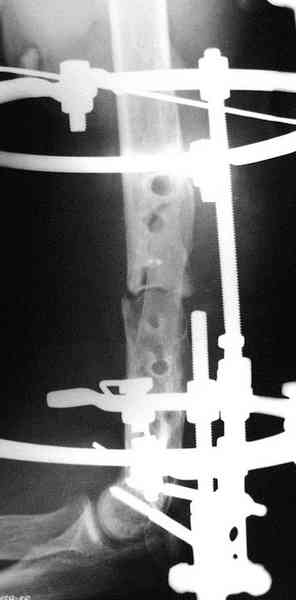

В подобном случае мы бы применили чрескостный остеосинтез. Пример - в приложении.